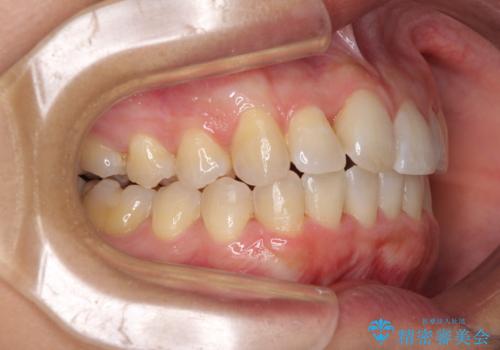

前歯のデコボコをインビザラインでスッキリと仕上げる

- 上下前歯のデコボコと奥歯の銀歯を気にして来院された患者様です。

口元をインビザラインにより歯列を整え、その後に失活している奥歯をオールセラミッククラウンにて補綴治療することとしました。

長時間のマウスピース装着に協力いただき、自然な口元に仕上げることができました。

気になっていた銀歯もオールセラミッククラウンで本物の歯のようになり、患者様には大変満足していただきました。